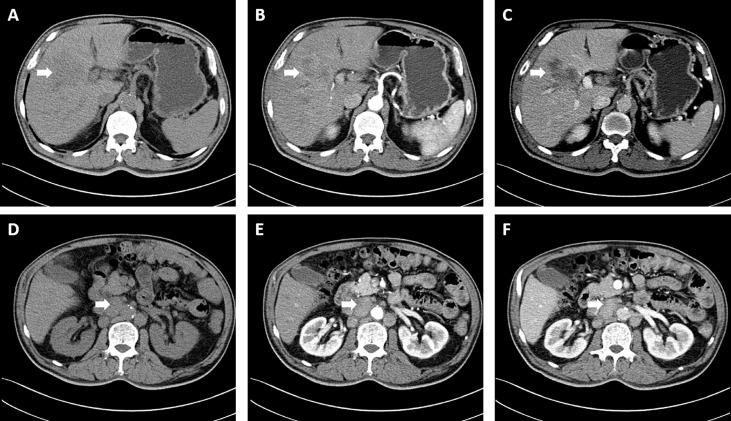

Intrahepatic cholangiocarcinoma (CCA), always diagnosed at an advanced stage in recent years, is of high aggression and poor prognosis. There is no standard treatment beyond first-line chemotherapy and no molecular-targeted agents or immune checkpoint inhibitors approved for advanced intrahepatic CCA. Hence, we firstly report an original therapeutic strategy for a 60-year-old patient diagnosed with intrahepatic CCA categorized as Stage IIIB (T3N1M0) by the American Joint Committee on Cancer staging system. After histopathological examination and next-generation sequencing, the patient was treated with four courses of novel systemic sequential therapy (intravenous gemcitabine 1,000 mg/m and cisplatin 25 mg/m on days 1 and 8; oral lenvatinib 8 mg/day from days 1 to 21; intravenous tislelizumab 200 mg on day 15). Then, the patient achieved partial response and was operated on right hemihepatectomy, cholecystectomy, and abdominal lymph node dissection. Without any perioperative complications, the patient was discharged from our hospital in perfect condition. Thereafter, the patient continued to use this new regimen 1 month after surgery for adjuvant therapy and was confirmed without recurrence when we followed up. In a word, we found an effective therapeutic regimen for preoperative advanced intrahepatic CCA conversion therapy, which may become a new approach in cancer treatment in the future.

肝内胆管癌(CCA)近年来往往在晚期才被诊断出来,具有高侵袭性和不良预后。除一线化疗外,尚无标准治疗方法,也没有针对晚期肝内CCA获批的分子靶向药物或免疫检查点抑制剂。因此,我们首次报告了一种针对一名60岁患者的原创治疗策略,该患者被美国癌症联合委员会分期系统归类为IIIB期(T3N1M0)的肝内CCA。经过组织病理学检查和二代测序后,该患者接受了四个疗程的新型全身序贯治疗(第1天和第8天静脉注射吉西他滨1000mg/m²和顺铂25mg/m²;第1天至21天口服乐伐替尼8mg/天;第15天静脉注射替雷利珠单抗200mg)。然后,患者达到部分缓解,并接受了右半肝切除术、胆囊切除术和腹部淋巴结清扫术。患者无任何围手术期并发症,康复出院。此后,患者术后1个月继续使用该新方案进行辅助治疗,随访时确认无复发。总之,我们找到了一种有效的术前晚期肝内CCA转化治疗方案,这可能成为未来癌症治疗的一种新方法。